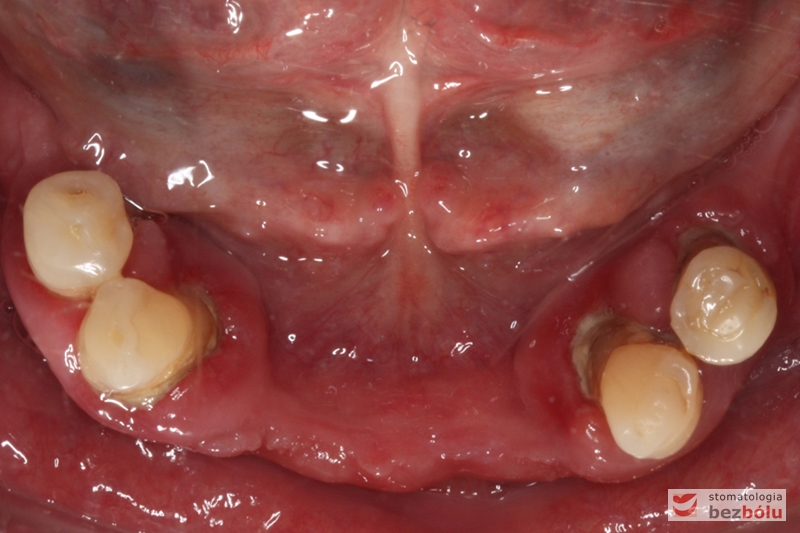

Widok łuku dolnego przed leczeniem

Stan wyjściowy - bez protez, liczne braki zębowe i po 2 nierokujące zęby w szczęce i żuchwie

Stan wyjściowy – bez protez, liczne braki zębowe i po 2 nierokujące zęby w szczęce i żuchwie